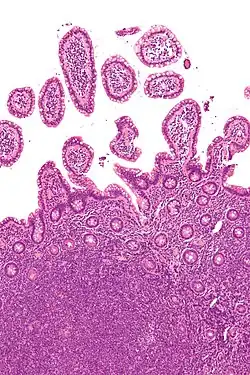

| Micrograph showing mantle cell lymphoma (bottom of image) in a biopsy of the terminal ileum. H&E stain. | |